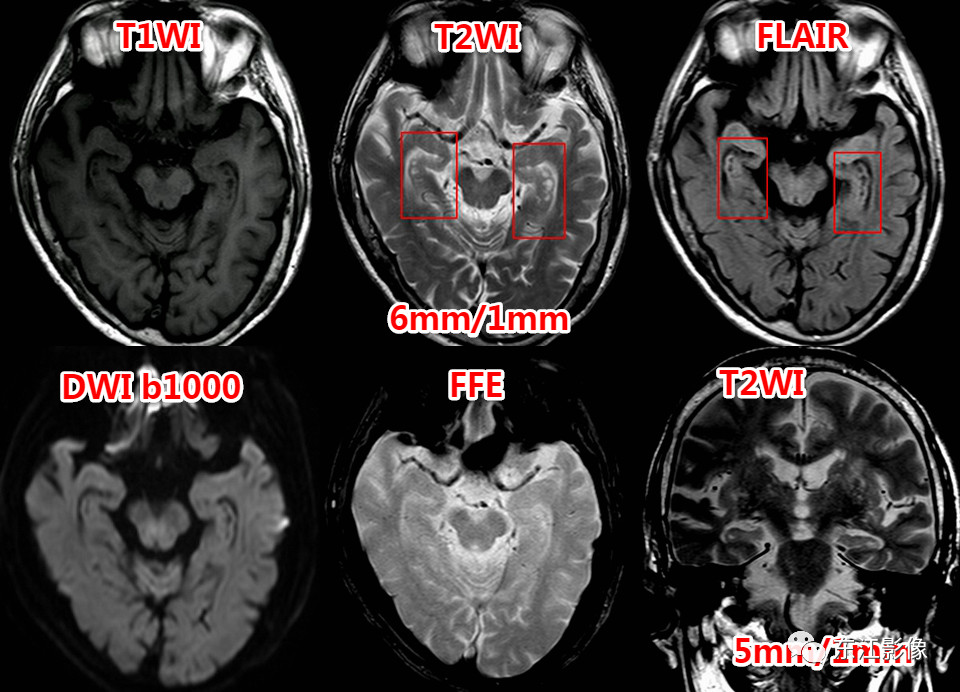

图2 又一例海马沟残余囊肿

图3 另一例海马沟残余囊肿,薄层显示更佳